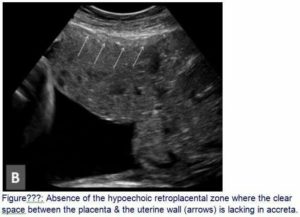

Пространство низкой эхогенности между маткой и плацентой является признаком преждевременной ее отслойки. Дополнительными признаками отслойки являются:

- гиперэхогенность одной из долей органа, возникшая как следствие кровотечения;

- образование кровяного сгустка, прилегающего к «детскому месту».